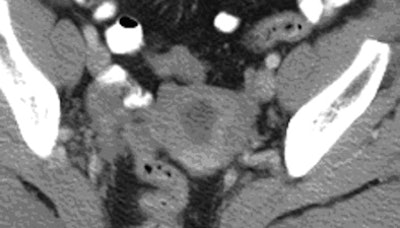

| Thirty-four-year-old woman with normal endometrium. Axial contrast-enhanced CT image (above) shows prominent triangular-shaped endometrium. Number 1 and circle indicate incidental measure of ovarian cyst not relevant to endometrium or this article. Sagittal reconstruction image (below) of same patient shows normal thin endometrium on this magnified image. Images courtesy of the American Roentgen Ray Society; from Grossman J, Ricci Z, Rozenblit A, et al. Efficacy of contrast-enhanced CT in assessing the endometrium. AJR. 2008;191:664-669. |